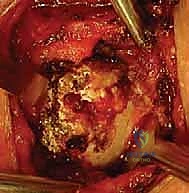

الخطوة 5: الإغلاق التجميلي

بعد التأكد التام من ثبات المفصل وعدم وجود أي احتكاك أو ضغط، يتم إغلاق الأنسجة والجلد بخياطة تجميلية دقيقة، ووضع المريض في حمالة كتف لحماية الإصلاح الجراحي.